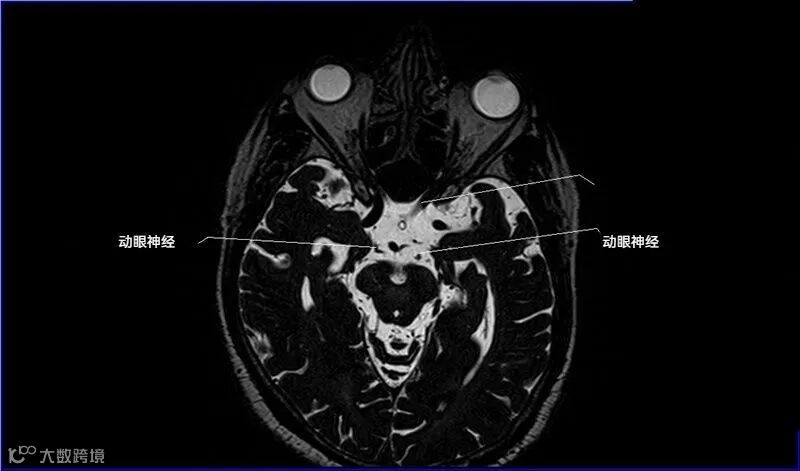

十二对脑神经口诀

一嗅二视三动眼,四滑五叉六外展,

七面八听九舌咽,迷走及副舌下全。